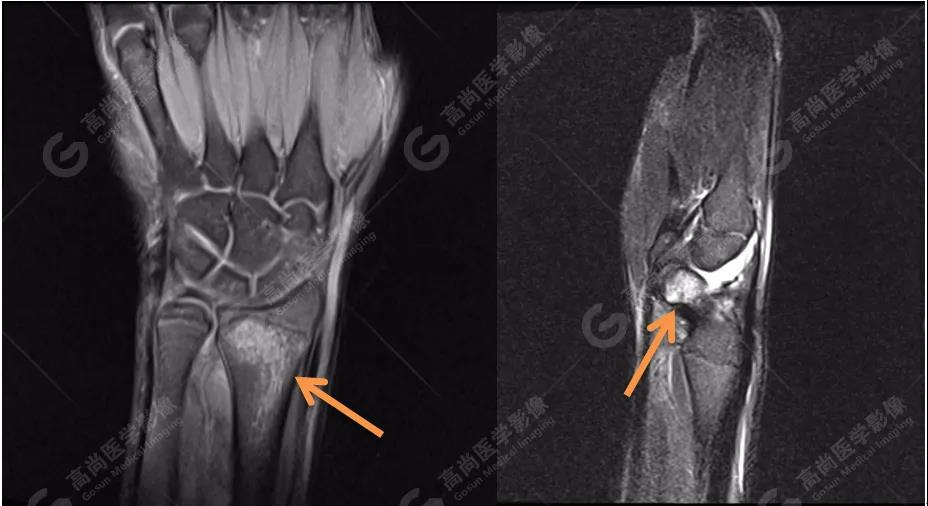

4、MRI圖像

MRI被認為是顯示骨髓水腫最好的方法。本著嚴謹、負責(zé)的態(tài)度,我們?yōu)椴』济赓M行MRI檢查,進一步確認診斷。

MR質(zhì)子壓脂序列圖像進一步證實:左側(cè)橈骨遠端與右側(cè)舟狀骨骨髓水腫!范圍也與雙能CT骨髓成像圖有很好的吻合度。